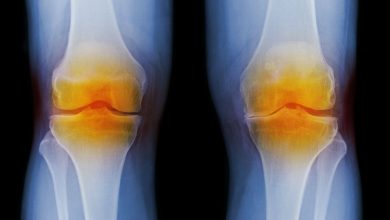

آرتروز بیماری ناشی از تحلیل دیسکهای بین مهرهای و غضروفهای مفاصل است که میتواند به استخوان نیز آسیب برساند و ممکن است در تمام مفاصل بدن اتفاق بیفتد. اما در افرادی که بهدلیل شرایط شغلی، گردن را در حالت نامناسب قرار میدهند، معمولاً به مهرههای گردن آسیب میرساند.

آرتروز گردن یک بیماری مزمن تلقی میشود که طی سالها بتدریج پیشرفت میکند و علائم آن معمولاً پس از 40 سالگی ظاهر میشود. در 50 درصد موارد، آرتروز گردن پس از عکسبرداری مشخص میشود و فرد هیچ علامت ناراحت کنندهای ندارد. البته بعضی افراد با درد ناحیه گردن در یک سمت کتف و پشت سر مواجه هستند. سردرد، خشکی گردن، احساس مورمور در دست به دلیل فشار به نخاع و حتی سرگیجه، اختلال در شنوایی، بینایی و تعادل ناشی از فشار مهرهها به شریان نیز از دیگر علائم هشدار آرتروز گردن شناخته میشوند.